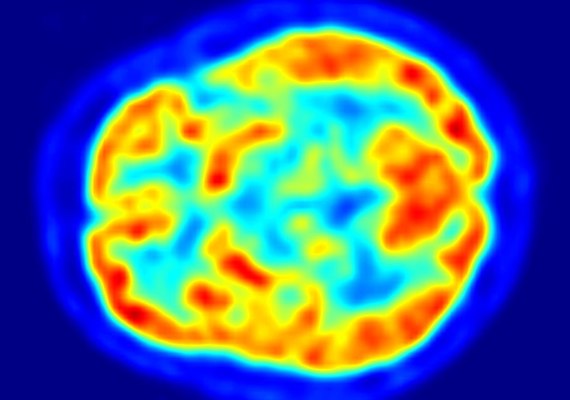

When Rylae-Ann Poulin was 1 year old, she did not crawl or make noises like other kids her age. A rare genetic disease prevented her from even lifting her head. Her parents took turns holding her all night to ease her breathing and help her sleep peacefully. But months later, doctors in Taiwan treated the young patient’s brain directly, attacking the disease with genetic medicine. Now the 4-year-old is walking, running, swimming, reading and riding horses. Rylae-Ann lives with her family in Bangkok, Thailand. She was accepted into a medical trial for a new method of gene therapy. Experts say the treatment holds great promise for treating several brain diseases. The method was approved in Europe and the United Kingdom for a condition called AADC deficiency. The disorder damages communication systems among nervous system cells. American drug company PTC Therapeutics plans to seek U.S. approval for the treatment this year. The National Institutes of Health (NIH) says there are about 30 studies underway in the United States right now to test gene therapy to the brain. The studies target a number of diseases. Dr. Krystof Bankiewicz at Ohio State University leads one such study on AADC deficiency. Others test treatments for brain diseases like Alzheimer’s, Parkinson’s and Huntington’s. Difficulties remain, especially with diseases caused by more than a single gene. But scientists say evidence is growing in support of gene therapy to the brain. “There’s a lot of exciting times ahead of us,” said Bankiewicz, a brain surgeon. “We’re seeing some breakthroughs.”